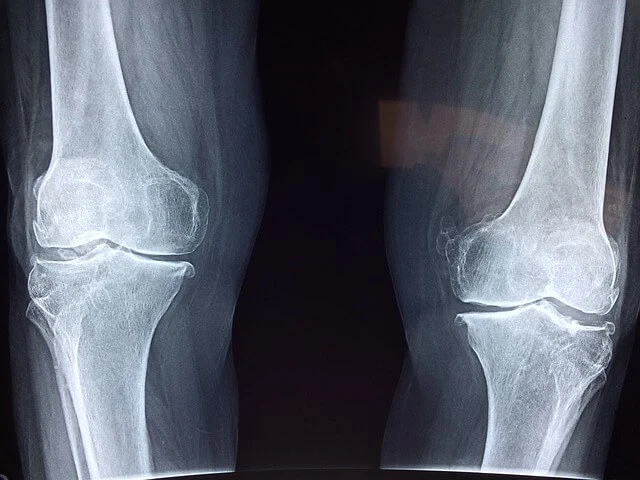

무릎 연골은 한번 손상되면 회복이 불가능한지 알고 계신가요?

무릎 연골은 사용량이 많아지면 마모와 늘어짐이 반복되면서 쉽게 파열될 수 있고, 혈액의 통행이 없어 무릎 연골이 한 번 손상되면 스스로 재생되지 않아 회복이 불가능합니다.